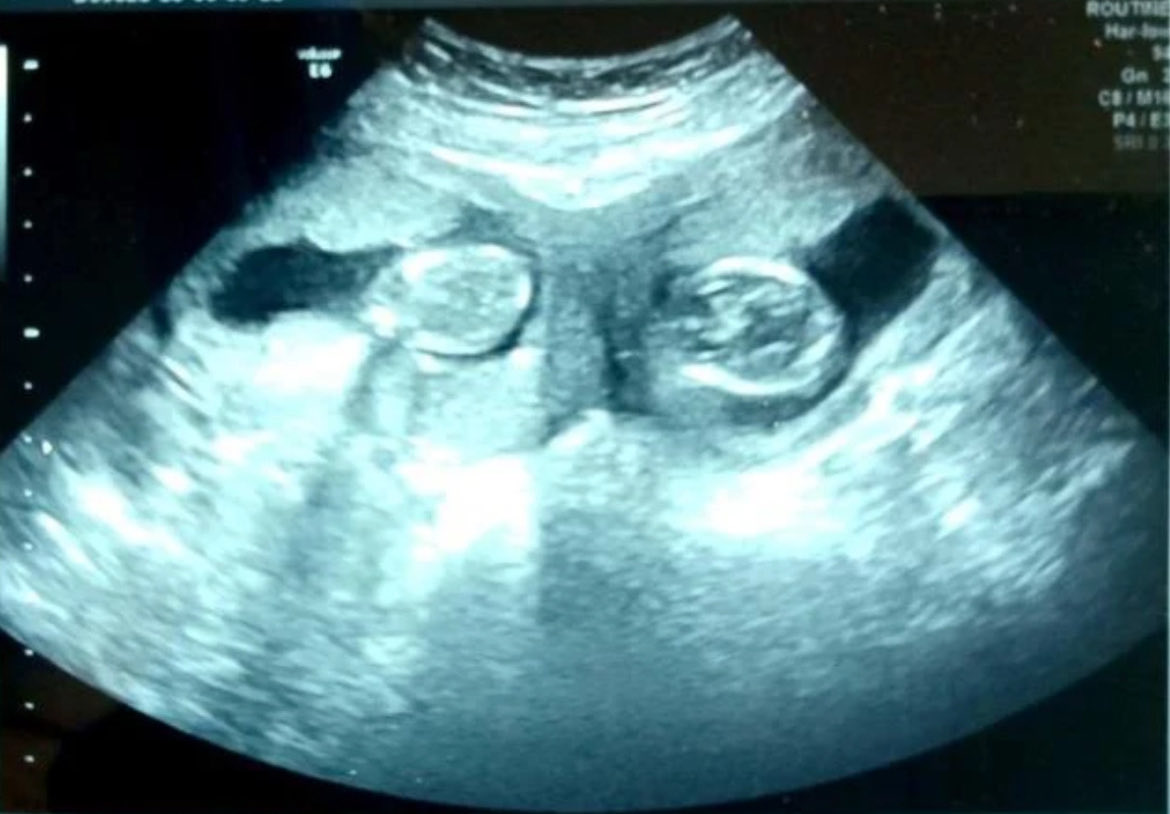

@alotoft7282_ Well... uh... congrats?

I hope things go well for you two.